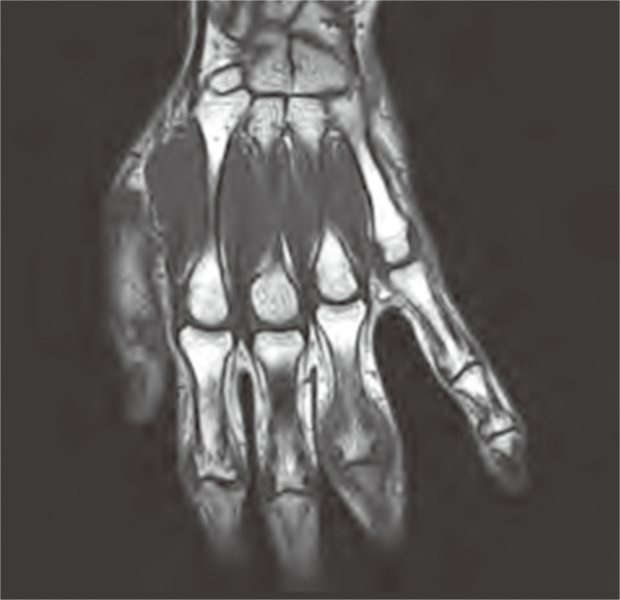

MRI検査とは強力な磁石と電波を利用することで体内の臓器や組織を画像化する検査法です。この検査では磁石の力や電波を使用しての検査なので放射線による被ばくはありません。当院では現在1.5T装置と3.0T装置が1台ずつで検査を行っています。このT(テスラ)は磁束密度の単位です。強い磁石ほど値が大きくなります。

3.0T装置では1.5T装置と比較し、磁石の力が強いのでよりきれいな画像を得ることができるため血管や神経、細かい場所を検査するのに適しています。しかし、体内の金属や体の構造による画像への影響は1.5T装置の方が3.0T装置よりも抑えられる場合があります。また、磁石の力が強いほど体への影響も大きく年齢や体格、妊娠の有無、手術歴などによって制限を受ける場合もあります。そのため、当院では検査の目的や患者さんの状態に合わせて1.5Tの装置と3.0Tの装置を使い分けて検査を行っています。